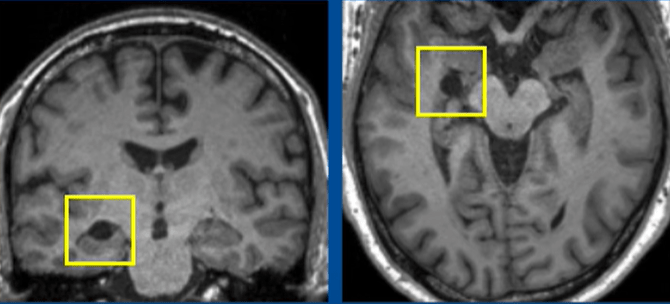

医生后来发现他的脑部出现一个大小约1厘米的圆形病灶,神经科医生推测病灶可能是左侧海马回的蛛网膜囊肿,其后诊断他患有罕见的神经系统疾病脸部变形症(Prosopometamorphopsia,PMO)。

▲医生其后发现他的脑部出现圆形病灶。(《The Lancet》图片)